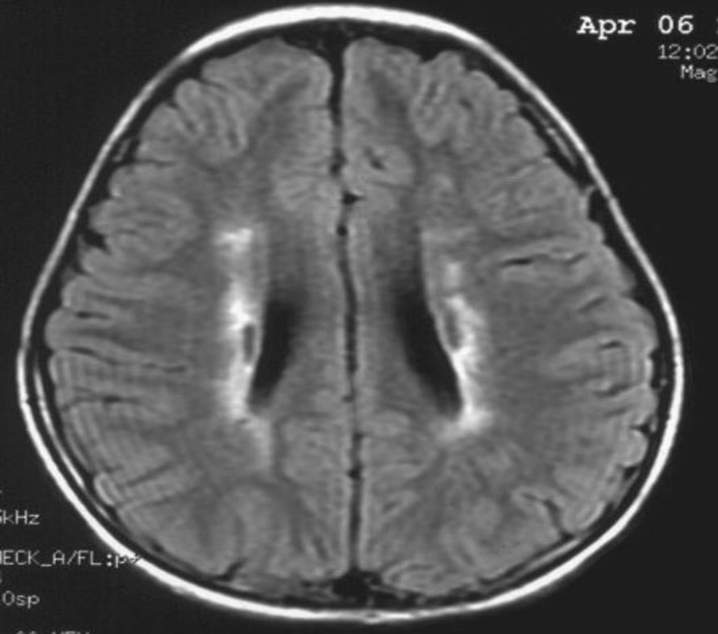

患者:林某某性別:男年齡:8 歲基本情況:出生后3個月臨床和頭部CT檢查診斷為腦癱。8年來病人曾在全國各地接受各種中西醫治療,病人入院時確診為痙攣性腦癱。治療時間:2005年7月接受干細胞移植手術。